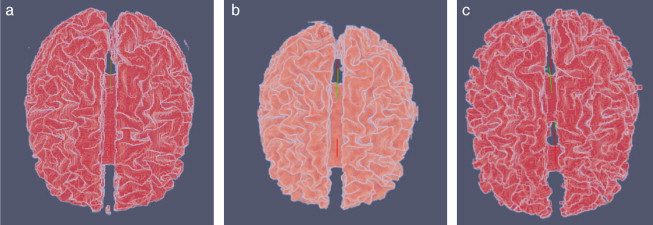

En la figura 26 son presentados las vistas tridimensional del volumen de la zona de la materia blanca proporcionado por BrainWeb, el volumen obtenido con Region Growing y volumen obtenido con Watershed.

|

|

|

Figura 26. Vista volumétrica de la zona de la materia blanca. (a) Volumen original de la materia blanca proporcionado por BrainWeb. (b) Vista 3D del volumen obtenido con Region Growing en la figura 26 .d. (c) Vista 3D del volumen obtenido con Watershed en la figura 27 .b. |